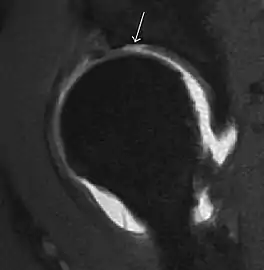

Most of the angles and measurements described in the plain radiograph section can be accurately reproduced on MRI. In addition, the superiority of MRI resolution with intra-articular contrast allows detection of labral and chondral abnormalities that may influence the choice of medical, percutaneous, or surgical management (Figure 9).[1]

Figure 9:

Sagittal T1 weighted image showing anterosuperior labral tear.[1]

Sagittal T1 weighted image showing chondral lesion.[1]

Sagittal CT-arthrography showing posteroinferior chondral injury.[1]

Coronal CT-arthrography (d) showing ligamentum teres tear.[1]

MR arthrography has proven superior in accuracy when compared to native MR imaging. It is considered the best technique to assess the labrum. Knowledge of the normal variable morphology of the labrum helps to differentiate tears from normal variants. A triangular shape is most commonly seen in 66% of asymptomatic volunteers, but round, flattened, and absent labra can also be found in asymptomatic populations. MR arthrography has demonstrated sensitivity over 90% and specificity close to 100% in detecting labral tears. Loose bodies are demonstrated as filling defects surrounded by the hyperintense gadolinium.[1]

Association between labral tears and chondral damage has been demonstrated. This underscores the interaction between cartilage and labrum damage in the progression of osteoarthritis. Chondral damage to the posteroinferior part of the acetabulum as a contrecoup lesion occurs in approximately one-third of pincer cases secondary to persistent abutment on the anterior part of the joint leading to a slight posteroinferior subluxation. This is considered a bad prognosis sign.[1]

MR arthrography can also demonstrate ligamentum teres rupture or capsular laxity, which are debated causes of microinstability of the hip. Elongation of the capsule or injury to the iliofemoral ligament or labrum may be secondary to microtrauma in athletes. MR can demonstrate abnormalities in these cases, such as increased joint volume or a ligamentum teres tear (Figure 9).[1]